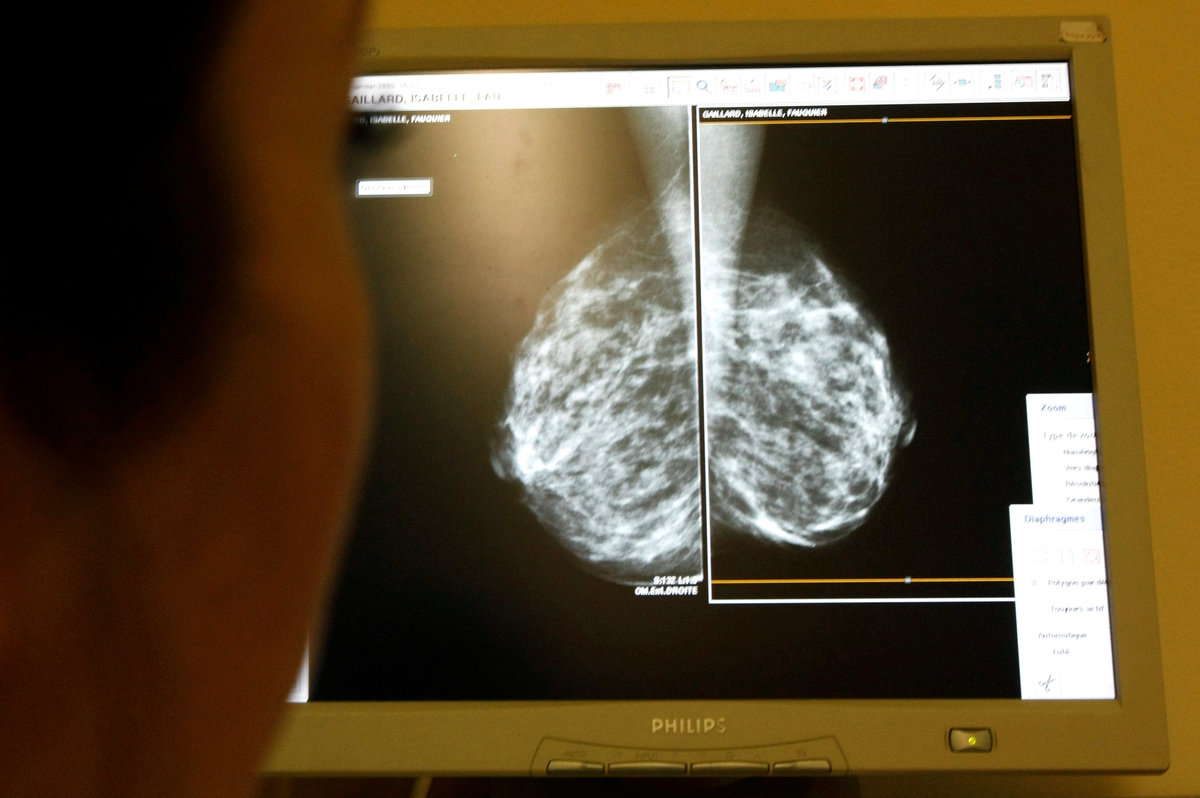

Under the routine NHS breast screening program, women aged between 50 and 70 are invited for tests every three years. Around 2 million women are tested every year.

The IT error affected some 450,000 women aged between 68 and 71, who should have received their final invitation to a test under the routine program but did not. Of those, around 150,000 have since died.

More than 300,000 of the remaining women, now aged 70 to 79, will be offered catch-up tests by the end of May, with all tests expected to be completed by the end of October.